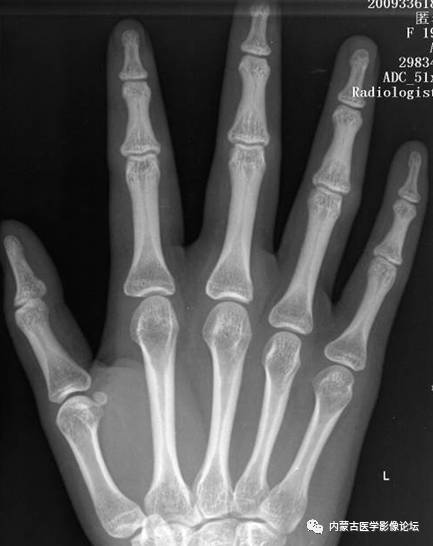

指骨骨皮质增厚:近、中节指骨骨皮质厚而致密,骨髓腔变窄,无病理学意义。